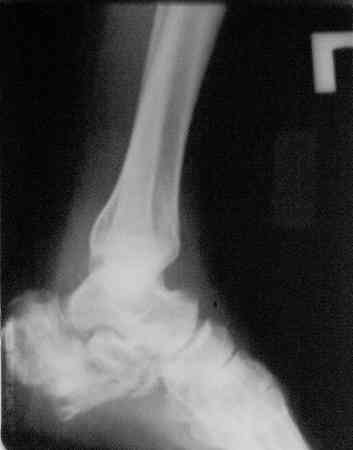

Уважаемый Дмитрий! Можете ли Вы добавить аксиальные проекции!

Присоединяюсь к мнению Я.Одесского о необходимости аксиальных снимков и, наверное, сразу снимков по Бродену (через каждые 10 градусов внутренней ротации стопы). Кроме этого необходима КТ. Она позволит уточнить срослись переломы или нет. Соответственно и тактика: если не срослись можно попробовать АВФ; если срослись -артродез.

Спасибо. Наверно, тут оптимален минимальный аппарат, позволяющий низвести бугор для восстановления формы стопы.

С левой стопой дело похуже. Нужен прямой снимок, да и боковой не помешает повторить на всю стопу, ну и плюс аксиальный. Готовтье аппарат.

Отправляю снимки(свежие)и фото стоп.

С уважениемД.Б.